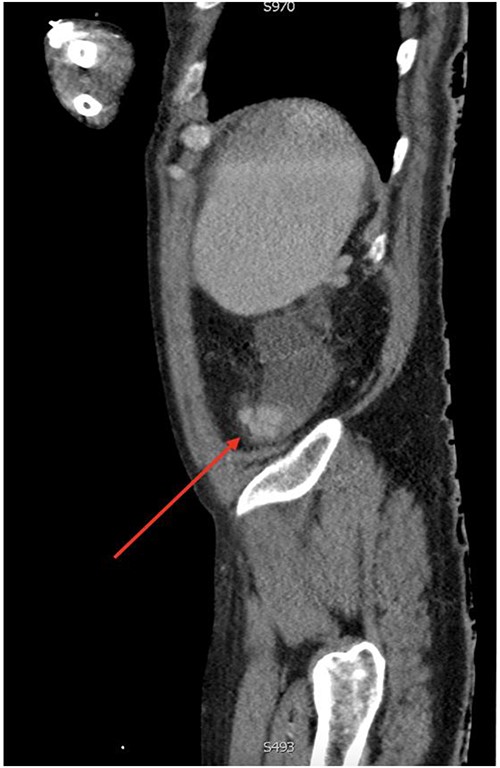

On gastroscopy, neither bleeding sources nor features of portal hypertension were identified. Subsequently, a large volume rectal haemorrhage occurred, resulting in severe hypotension and syncope. The patient was resuscitated appropriately and received a massive transfusion protocol. A CT angiogram revealed focal clustered varices travelling retroperitoneally abutting the caecal pole (Fig. 1), which communicated with a large branch of SMV in the right iliac fossa (Fig. 2).

Sagittal view of computerized tomography imaging in portal venous phase with arrow marking varices at the caecum.